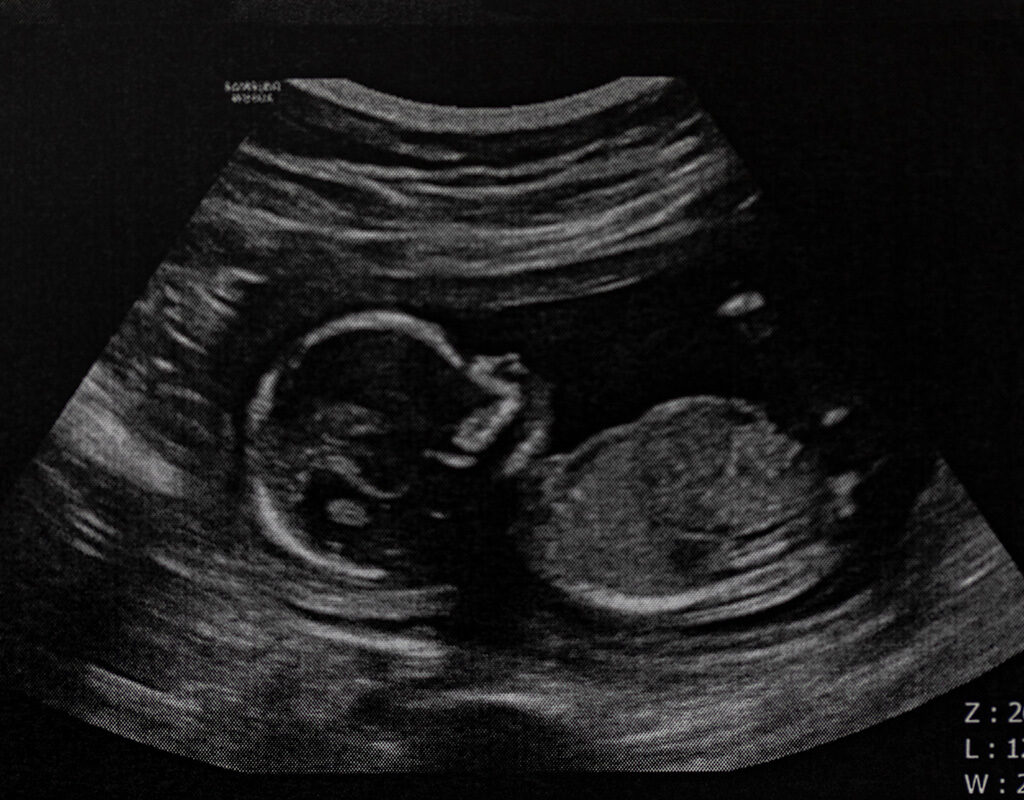

Woman sues abortionist for $250K over perforated uterus, dead baby’s skull fragments in intestine